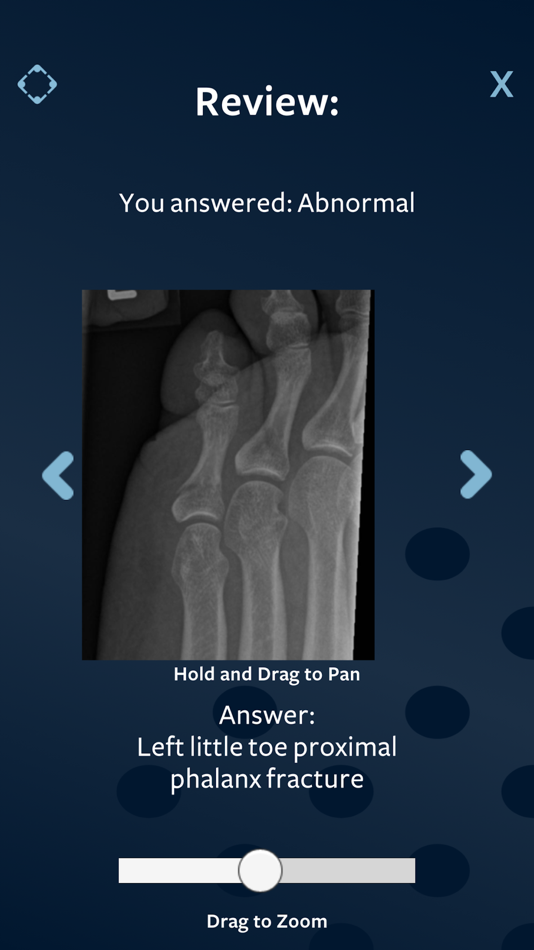

Find the Normals

This game is aimed at helping you become more confident at spotting normal x-rays.

The danger with calling a normal x-ray abnormal, is that it can lead to excessive investigation and patient anxiety, as well as the risk of exposing the patient to unnecessary radiation.

The skill of picking up normal x-rays is tested during the Rapid Reporting section of the Final Part B examinations of the FRCR (Fellowship of the Royal College of Radiologists).

Simply choose the difficulty of X-Rays you’d like to practice and get instant feedback on whether you got it right or wrong. You can review your answers after the timer runs out and see whether you picked up the normals. You also get to see the diagnoses of the abnormal x-rays. Try to improve on your results to become faster and more accurate.